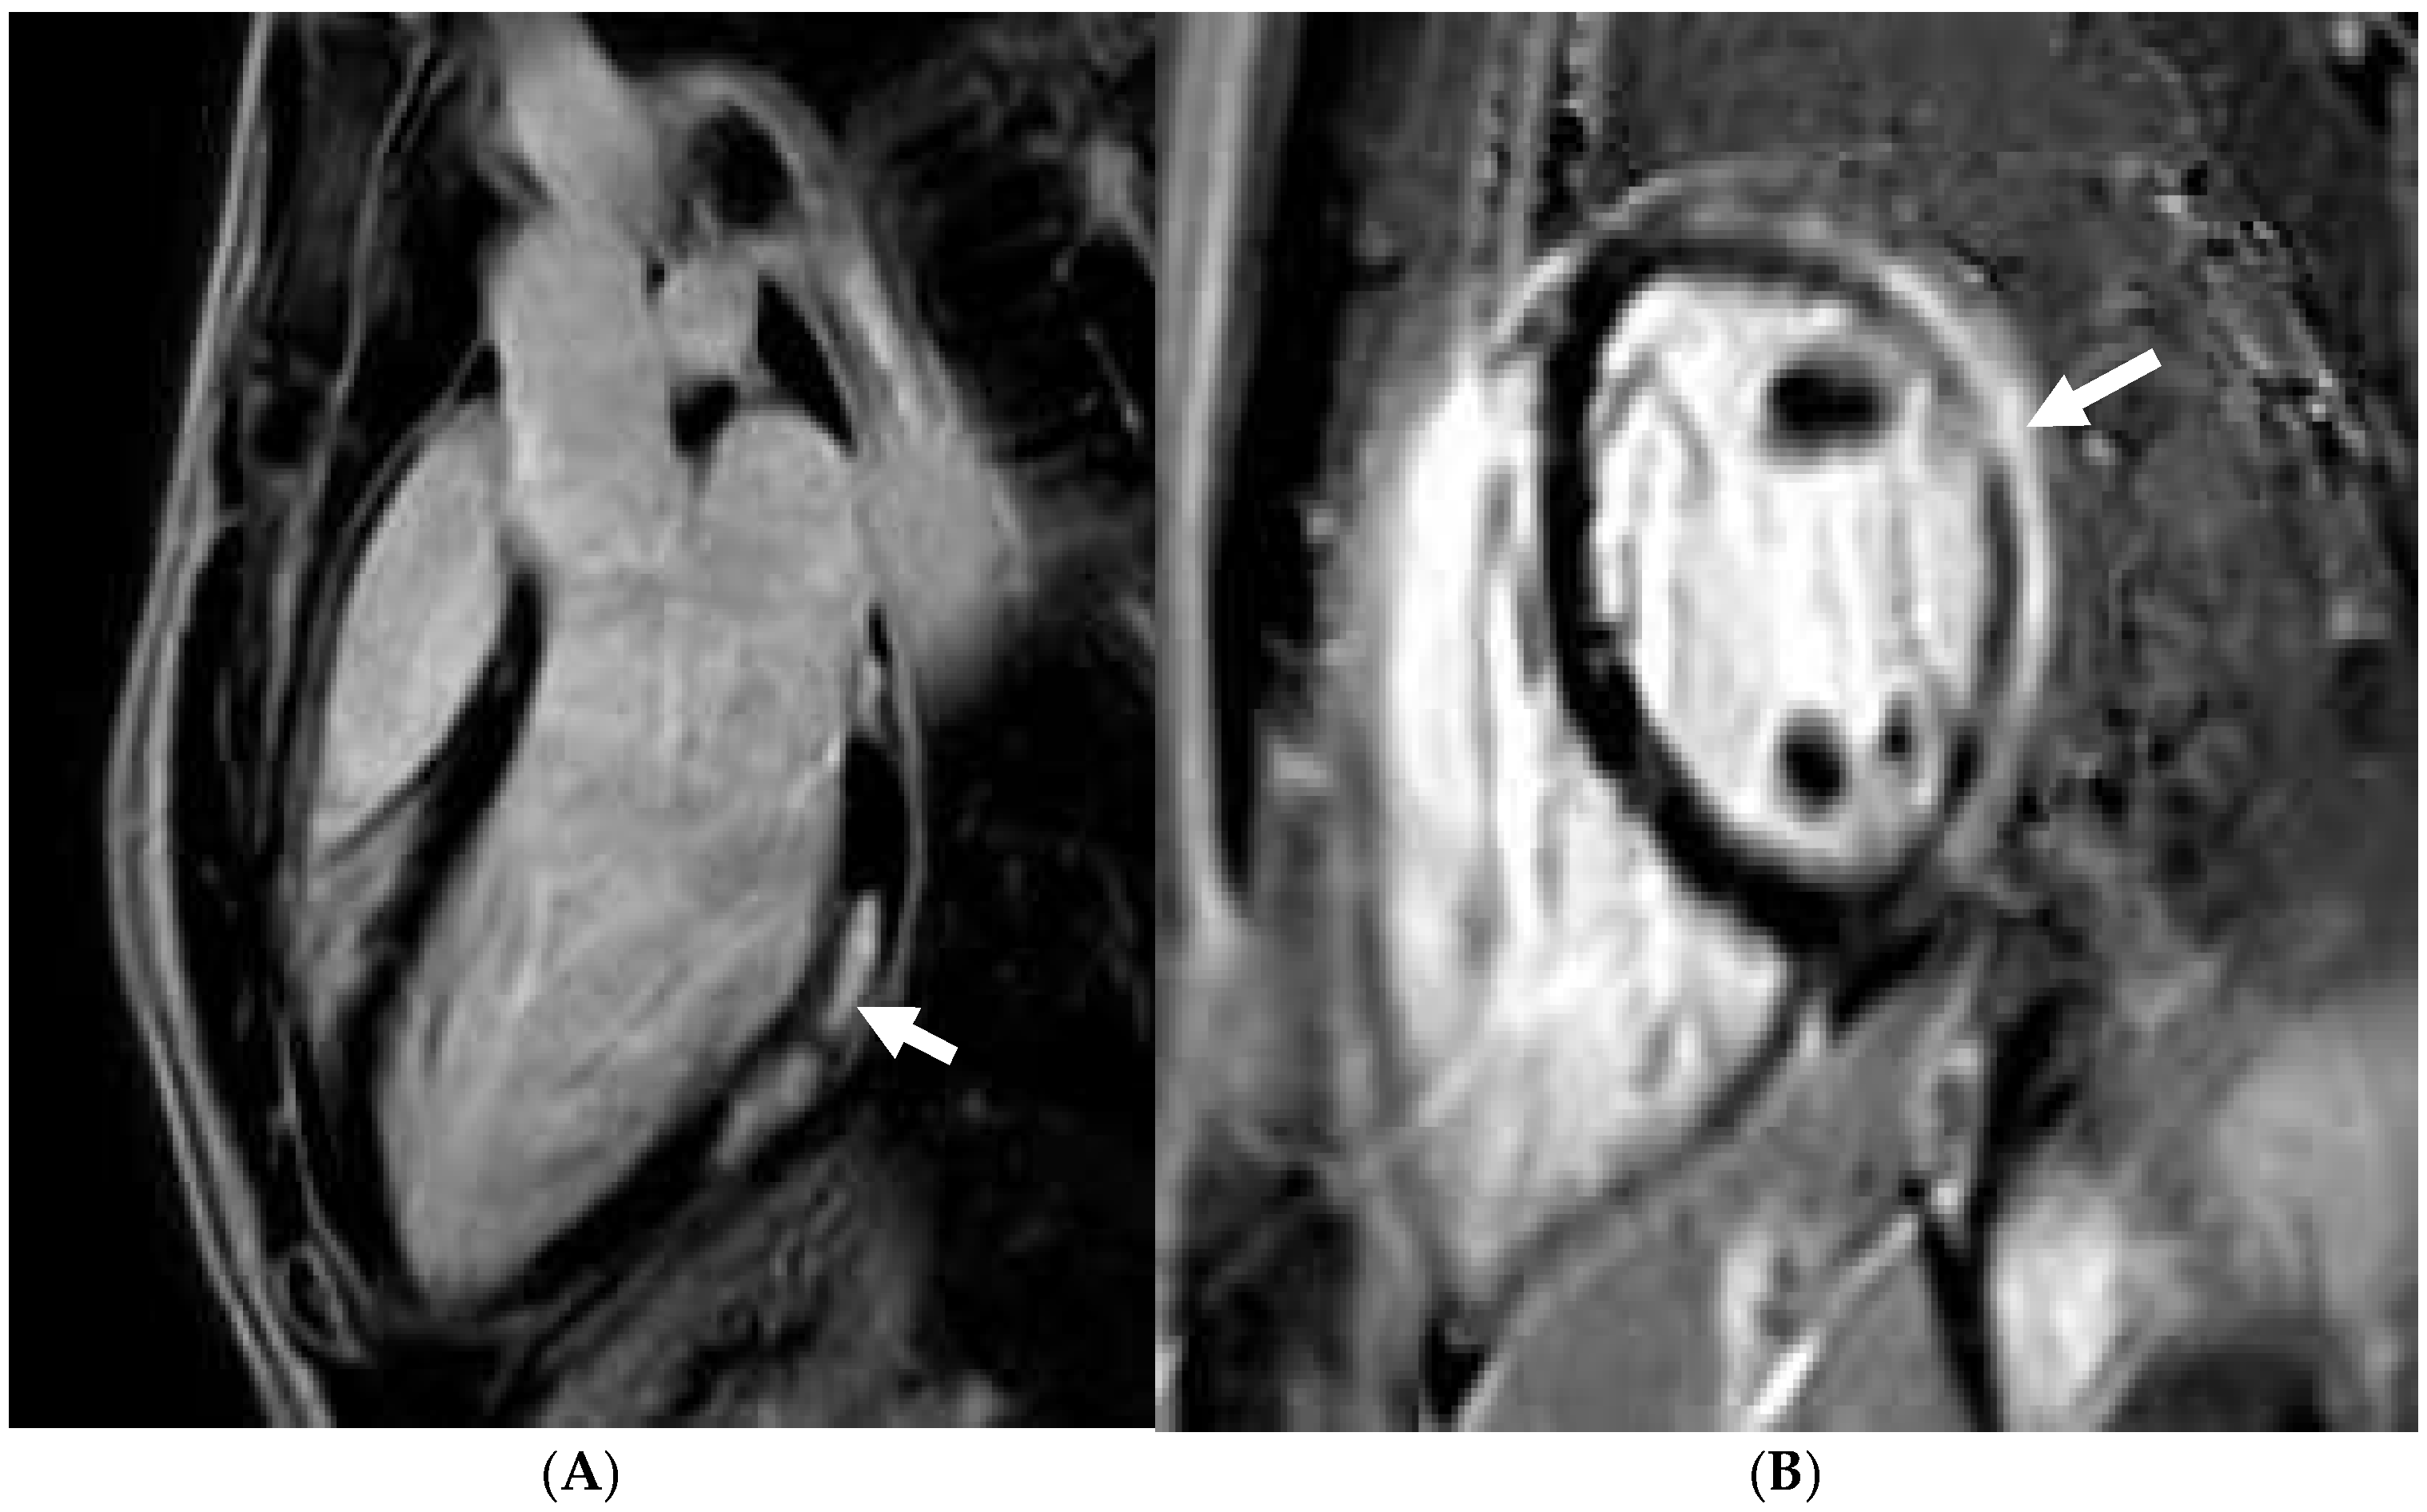

3.3. Technical Challenges—Practical Tips

7. Hypertrophic Cardiomyopathy